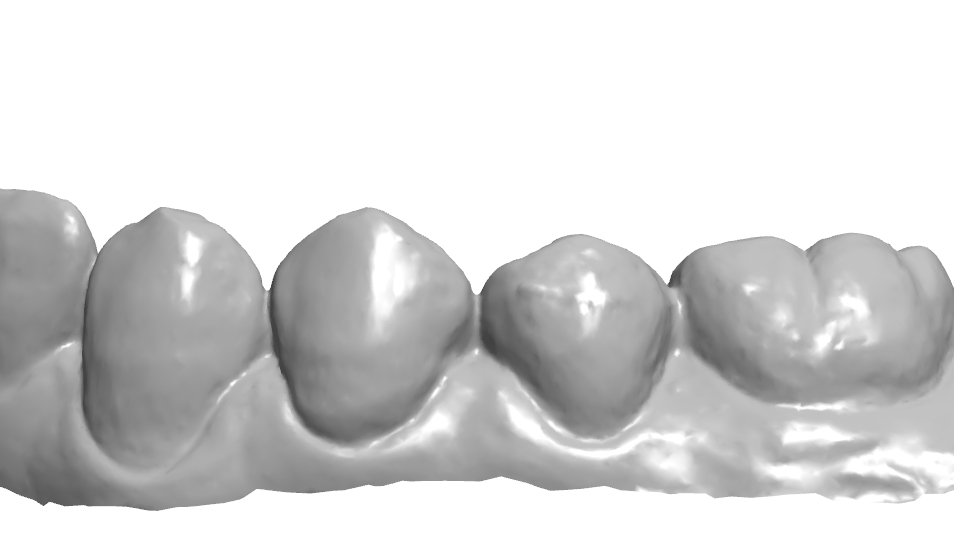

34번이나 35번을 생각보다 모양 잡기가 어려운것 같아 여러 방향에서의 모습을 찍어놓고

가끔식 보고자 하여 이렇게 기록으로 남겨본다.

협측에 있는 엠브레져 체크.

치경측에 존재하는 협측, 설측 엠브레져 체크.

협측 풍융도 체크.